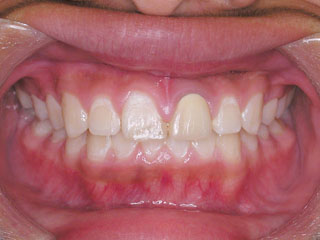

2年半ほどの治療で、装置を撤去し保定治療に移行しています。飛び出ていた前歯も、下の歯と正しく噛めるようになりました。口元の突出も消え、口唇閉鎖時に前歯が覗いて見えるという事も無くなりました。